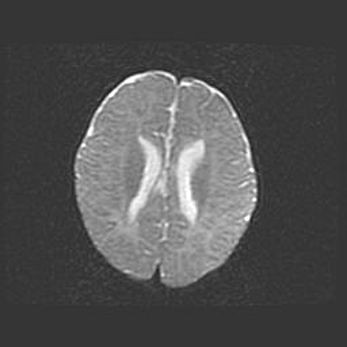

Наружная гидроцефалия с возможной атрофией височных областей.

Возраст: 28 дней

Вес: 3670 г

Пол: мужской

Окружность головы: 38 см

Срок гестации: 40 недель

Гидроцефалия головного мозга у новорожденных – это заболевание, которое характеризуется скоплением избыточного количества спинномозговой жидкости в желудочковой системе головного мозга в результате затруднения её перемещения от места выработки к месту поглощения в кровеносную систему или вследствие нарушения абсорбции. При открытой наружной форме гидроцефалии у новорожденных расширяются и переполняются субарахноидные пространства.

При нормотензивных  формах,  которые,  как  правило,  являются  следствием  перенесенных ишемических  повреждений  паренхимы  мозга,  возможно  сочетание микроцефалии  с нормотензивной гидроцефалией. В основе данных изменений лежит атрофия больших полушарий с преимущественной  локализацией  в  лобно-височных  областях.